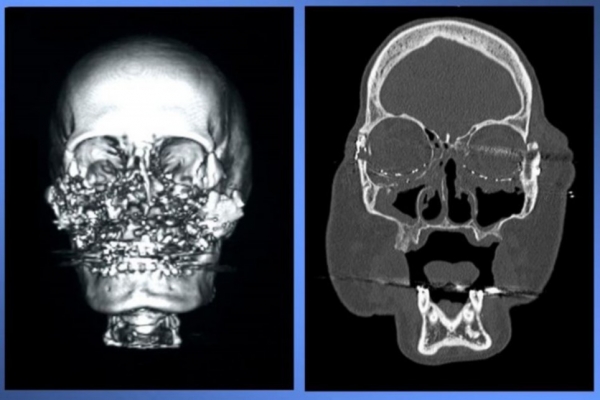

ونجا الزوج من الحادثة، بعدما أطلق النار على نفسه؛ حيث عانى من تشوهات في فكه السفليّ، وفي عام 2005 تم الحكم عليه بالسجن 7 سنوات. بينما كانت كوني بين الحياة والموت، بعد أن حطمت الطلقة أنفها وخديها وسقف فمها وإحدى عنينها، وتركت فجوة كبيرة في الوجه، هذا فضلا عن التصاق مئات الشظايا جراء الطلقة النارية في عظام وجهها. وبعد جراحة عاجلة فور الحادث، تمكنت كوني من التنفس عبر أنبوب تمت زراعته في القصبة الهوائية.

خلال عملية جراحية استمرت 22 ساعة في “كليفلاند كلينيك”، تم استبدال 80% من وجه كوني، وحصلت على أنف وشفة عليا وفم وجبهة أسنان. وبعد الطلاق انتقلت كوني إلى شقة جديدة، وبدأ يتحدث مع غيرها من ضحايا العنف المنزلي والعنف، وقالت إنها تفكر الآن في كيفية تجنب أي مواجهة مع زوجها السابق الذي سيخرج من السجن الخريف المقبل.